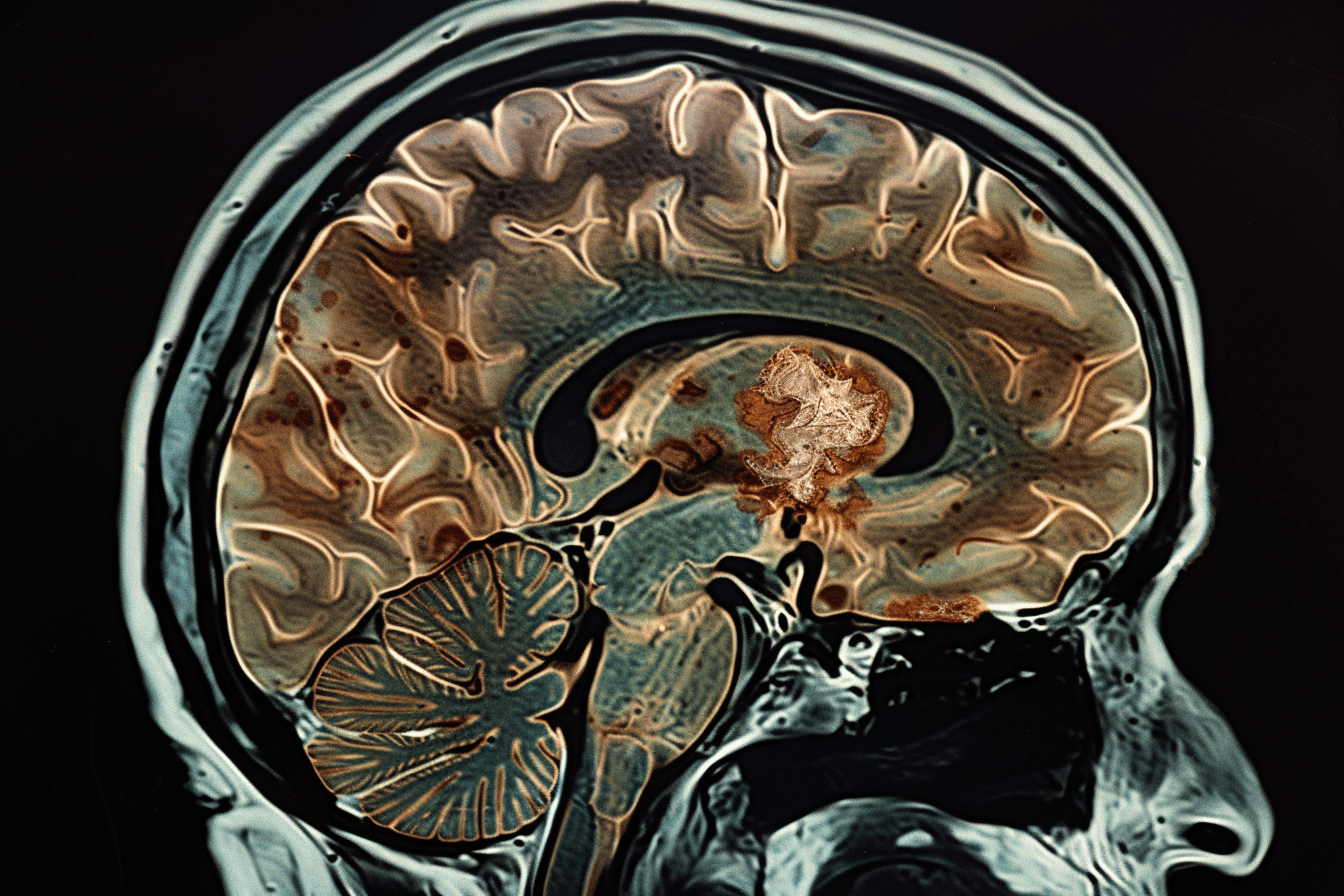

Diffuse Infiltration Into Surrounding Brain Tissue

Gliomas do not stay confined to one location. They spread into nearby brain tissue in a scattered and microscopic pattern. Even when scans show a defined tumor, individual cancer cells have already moved beyond that visible area.

During surgery, only the main tumor mass can be removed. The scattered cells that mix with normal brain tissue cannot be safely taken out without damaging essential functions like speech or movement. Because of this, some tumor cells almost always remain after surgery, which later leads to regrowth [2].

Tumor Microenvironment and Regrowth

After treatment, the remaining tumor cells do not exist in isolation. They interact with the surrounding brain environment, which plays a major role in helping them survive and grow again. This surrounding space, known as the tumor microenvironment, includes blood vessels, immune cells, supporting brain cells, and chemical signals.

Even when most of the tumor is removed, this environment can still support the survival of residual cells. It provides the conditions needed for these cells to remain active and eventually regrow [11].

Instead of dying, tumor cells can adapt to this low-oxygen environment. In fact, hypoxia can make them more aggressive. It activates survival pathways, increases resistance to therapy, and promotes further tumor growth. This gives the remaining cells a strong advantage in rebuilding the tumor [12].

As tumor cells begin to grow again, they need a steady supply of oxygen and nutrients. To achieve this, they stimulate the formation of new blood vessels, a process known as angiogenesis.

This new vascular network allows the tumor to expand and sustain itself. Angiogenesis is not just a late event. It begins early in the regrowth phase, often before the tumor becomes visible on imaging. This is one of the reasons why recurrence can progress rapidly once it starts [11].

Under normal conditions, the immune system can recognize and destroy abnormal cells. However, glioma cells develop mechanisms to escape immune detection.

They can suppress immune responses, alter signaling pathways, and create a local environment that protects them from immune attack. This allows tumor cells to grow silently without being eliminated by the body’s natural defenses [12].